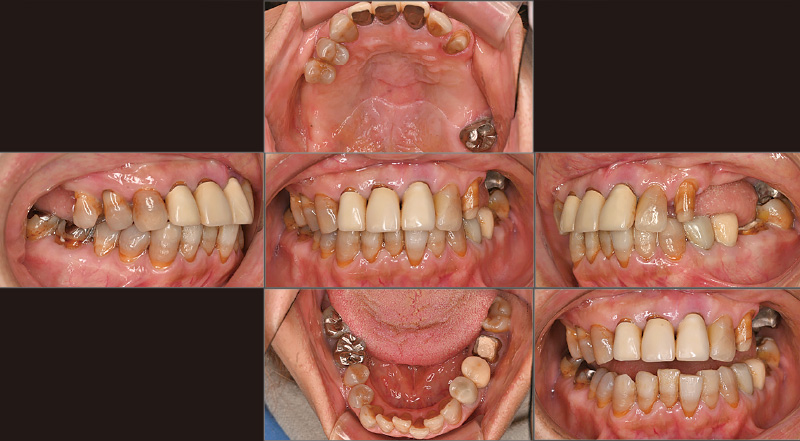

症例の患者さんは「奥歯でものが噛めない」という主訴で初めて来院されました(図1)。義歯治療を行い、いったんは噛めるようになりましたが、噛める位置だけで噛み続けていたためか、徐々に義歯が不安定になり、5年後に再び来院されました(図2, 3)。そこで、義歯を撤去し、インプラント治療に加えて、第一大臼歯まで矯正可能な「iGo Plus」による矯正治療を提案しました。最初に「iGo Plus」のクリンチェック治療計画を行い、矯正治療後の位置を考慮し、インプラント治療の埋入計画を立て、双方の診断画像を照らし合わせ、最終的なインプラント埋入位置を決定しました。計画した位置にインプラントを埋入し(図4)、プロビジョナルを装着しました。その後「iGo Plus」によるクリンチェック治療計画を再度行った後(図5, 6)矯正治療を開始し(図7)、当初の計画通りに矯正治療を完了しました(図8)。ここまでしておけば、噛めなくなる事態は回避できるでしょう。私たちの役目は、咬合状態を回復し、噛める状況まで持っていくことです。その後、審美性を求めて治療を続けていくかは患者さんの判断に委ねます。症例の患者さんの場合は、これから前歯の審美治療を行う方向で相談中です。

図1 初診時。60代女性。2019年9月、「奥歯でものが噛めない」という主訴で当院を来院。義歯治療によって咀嚼機能の回復を図った。 -